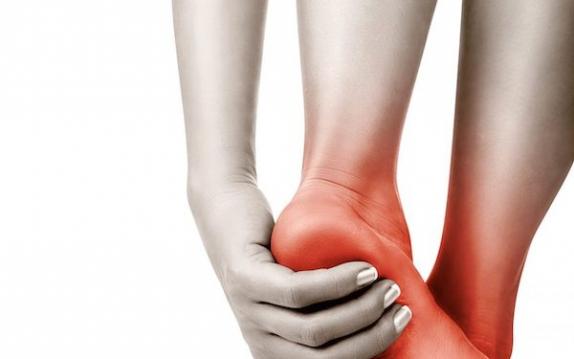

Ayaklarda Karıncalanma Oluyorsa

Nöroma nedir? Ayaklardaki yanma ve ağrı sorunlarının kaynaklarından biri nöromalardır. Ayaktaki sinirlerin etrafındaki bağ dokusunun genişlemesi ve iltihaplanması sonucunda ortaya çıkan, yanma, ağrı, karıncalanma, huzursuzluk hissi, kramp ve duyuda bozulma gibi şikayetlerle kendini gösteren bir durumdur. Morton nöroma ayakta en sık görülen nöromadır. Özellikle 30 yaş üstünde ve kadınlarda sıklıkla görülmektedir. Genelde uygunsuz ve topuklu ayakkabı kullanımına bağlı olarak ortaya çıkmaktadır. Ayaktaki 3. ve 4. parmakların metatarsal kemiklerinin arasındaki siniri sıkıştırmasına bağlı olarak ortaya çıkmaktadır. Belirtileri; problemin olduğu bölgede yanıcı ağrı, hissizlik, buruşuk çorap duyusu, keskin ve/veya yayılan ağrı ve ayakkabı giyildiğinde artan, çıkarıldığında azalan ağrı olarak sıralanabilir. Nöroma nasıl tedavi edilmektedir? Nöroma ağrısı ayakkabının çıkarılması ve bölgeye masaj yapılması sonucunda genellikle azalmaktadır. Tedavi için geniş ayakkabılar, çeşitli ayak veya parmak pedleri ve ağrılı bölgeye kortizon enjeksiyonları uygulanabilmektedir. Bu tedavilerin yetersiz kaldığı durumlarda cerrahi tedaviye başvurula bilmektedir. Metatarsalji nedir? Ayak tabanında metatars kemikleri olarak da bilinen tarak kemiklerinin bulunduğu bölgedeki ağrıya “metatarsalji” denilmektedir. Travma, uzunluk farklılıkları, düztabanlık, halluks valgus, halluks rigitus gibi yapısal deformitelere, bazı bozukluklara, kemik ve yumuşak doku bozukluklarına bağlı oluşabilmektedir. Hastalarda tarak kemiğine ve eklemine dokunulduğunda ağrı ortaya çıkmaktadır. Ayrıca ayak tabanında tarak kemikleri altında taş varmış hissine neden olmaktadır.